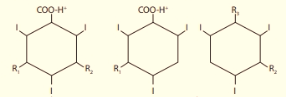

Um tipo de contraste radiológico, sua molécula é composta de um anel de seis membros tri-iodado com duas cadeias orgânicas laterais e um grupo carboxil. Observe a figura e sua estrutura:

A solução do contraste composta por estas três moléculas, são chamadas de meio de contraste: